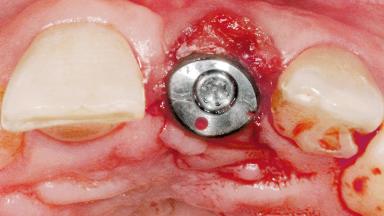

Late Flapless Placement of an Implant in a Maxillary Left Central Incisor Site

Type of Implants One-Piece

Attachment One-Piece

Abutment Type Standard

Placement Protocol Early or late implant placement